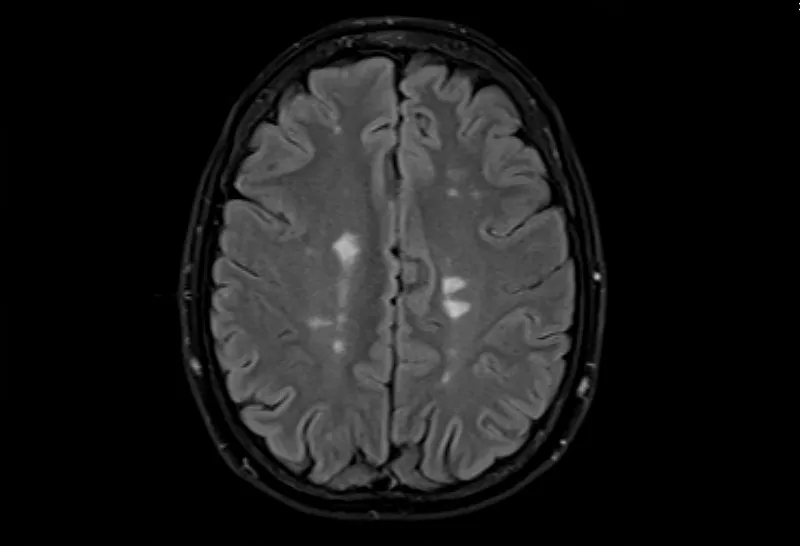

- 大腦的MRI掃描可以顯示損傷區(qū)域,但沒有單一的測試可以診斷MS。

測試的組合用于診斷MS。最好的測試是對您的大腦和脊髓進行核磁共振檢查,以檢測損傷區(qū)域。您可能還需要進行血液檢查、腰椎穿刺和測量神經(jīng)活動的測試。